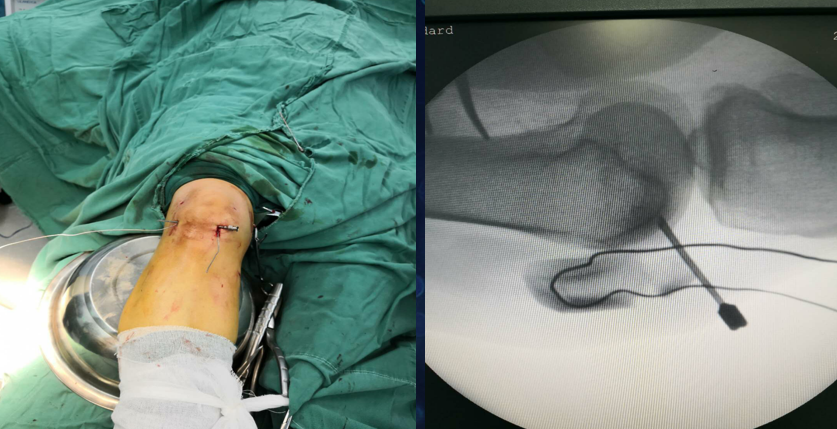

点氏复位钳经皮复位打入一克氏针临时固定

用电钻在髌骨上下极打一骨洞,用腰穿针带过钢丝

紧贴钢丝上方打入两髌骨针

折断髌骨针后再次收紧钢丝

术中照